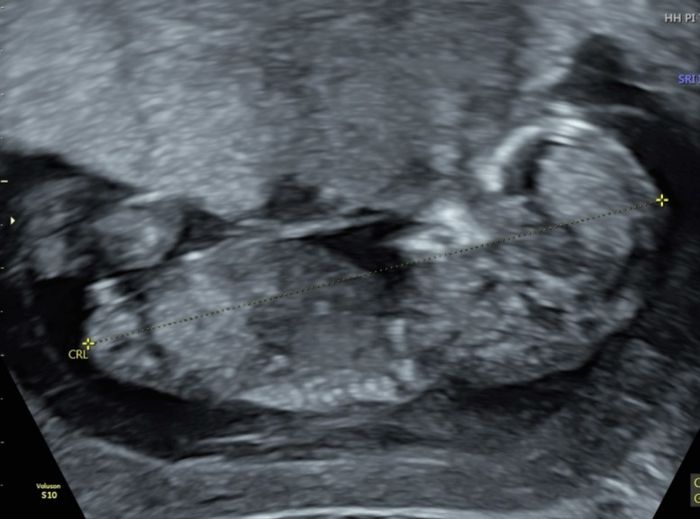

Nub theory, giochiamo un po’

Da Elena , Il 4 Gennaio 2025 alle 15:48

Ciao ragazze, lunedì scorso ho fatto eco genetica a 11+5 ma bebè misurava 12 settimane, ho fatto dna fetale che dovrebbe arrivare questa settimana, ma nel frattempo per...